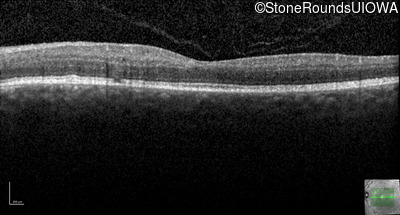

The clinical features supporting the diagnosis of the enhanced S-cone syndrome (ESCS) in this patient include: stable night blindness since at least the second year of life, normally sighted parents, nummular pigment in the mid-periphery of the fundus that stops abruptly at the temporal arcades and disorganization of the retinal layers (seen on OCT) anterior to the temporal arcades.